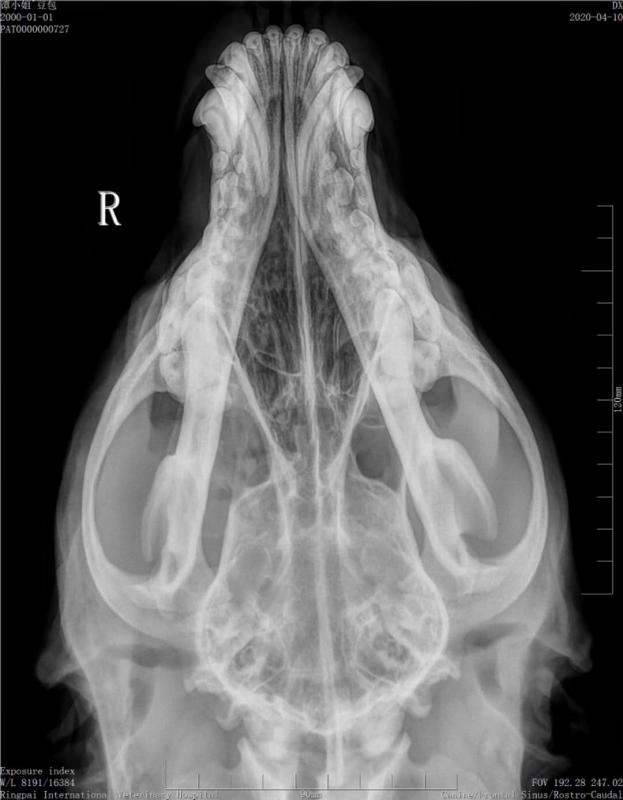

术前影像